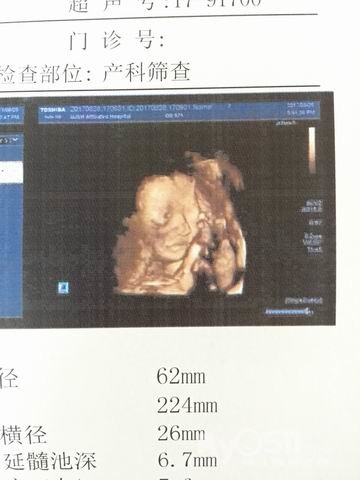

自从怀孕,陪伴我的都是各种检查报告单,验血、等报告。。。不过看到肚子里的小家伙那种心情还是很美丽的~(怀个孕不知道抽了多少血。。。

一直以来,小布丁都很顽强,棒棒哒~这个月底就要做四维了,咱们继续努力哈~

篇三:孕期的日常生活~目前为止,小布丁已经23周+了,近期能够感受到胎动,还录了小视频给小布丁爸爸看,有时候生命真的很神奇~就如同天边的彩虹,有着一种魔力!